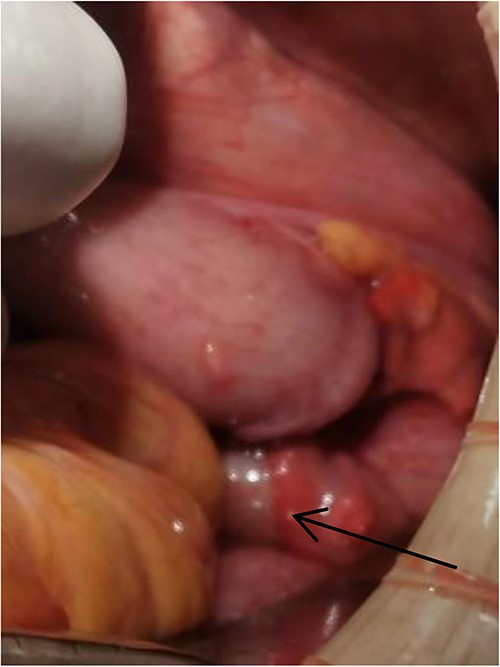

Tumor (indicated by black arrow) on the ascending colon observed during operation.

Laparoscopic exploratory laparotomy and obturator hernia repair were performed. A 4 × 4 cm thick hard tumor was observed in the ascending colon near the liver curve, involving serosa, and the ascending colon was partially blocked. A total of 80 cm away from ileocecum, the intestine entered from the right obturator hernia, causing obstruction and expansion of the proximal intestinal canal, congestion, and edema of the intestinal wall. We aspirated the ascites, loosened the adhesion around the obturator hernia ring, and returned the small intestine back into the abdominal cavity. It was observed that the intestinal wall of the hernia section was ~4 cm, necrotic, and broken, and the intestinal contents were flowing out, the intestinal defect was immediately closed, the abdominal cavity was flushed with normal saline, and the peritoneum at the obturator was intermittently sutured and repaired. A median abdominal incision of ~12 cm was used to cut each layer of the abdominal wall, enter the abdomen, protect the incision, lift out the intestine at the breach, place the aspirator in the intestinal lumen, aspirate large amount of intestinal contents, and temporarily close the breach. The abdominal and pelvic cavities were rinsed again with plenty of normal saline. With the consent of the patient’s family, a double-cavity ileostomy was successfully performed.